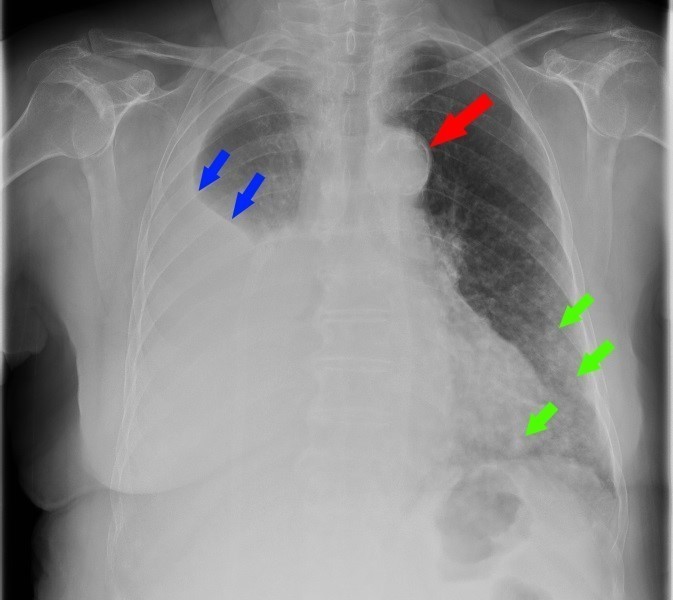

Le siège de la douleur est atypique mais n’élimine pas formellement un syndrome coronarien surtout chez un sujet âgé (pouvant se manifester de manière atypique), présentant de nombreux facteurs de risque cardiovasculaire (âge, HTA, dyslipidémie, tabagisme actif).

À évoquer en priorité car TVP récente et douleur thoracique. Le traitement anticoagulant en cours n’élimine pas une migration embolique (surtout en cas de mauvaise observance).

À évoquer devant une douleur thoracique latéralisée.

À évoquer devant une douleur thoracique latéralisée chez une patiente avec tabagisme important.